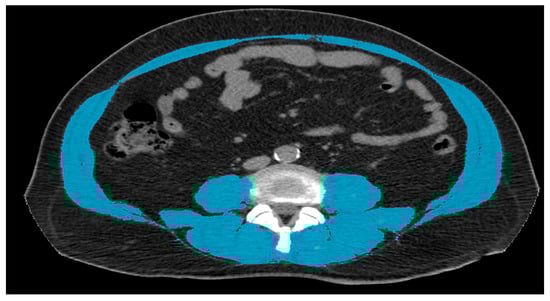

| Muscular Area | Fistula Present | No Fistula |

|---|---|---|

| Patients | 16 | 41 |

| Average | 98.1 | 94.2 |

| MIN | 61.9 | 38.7 |

| MAX | 154.5 | 217 |